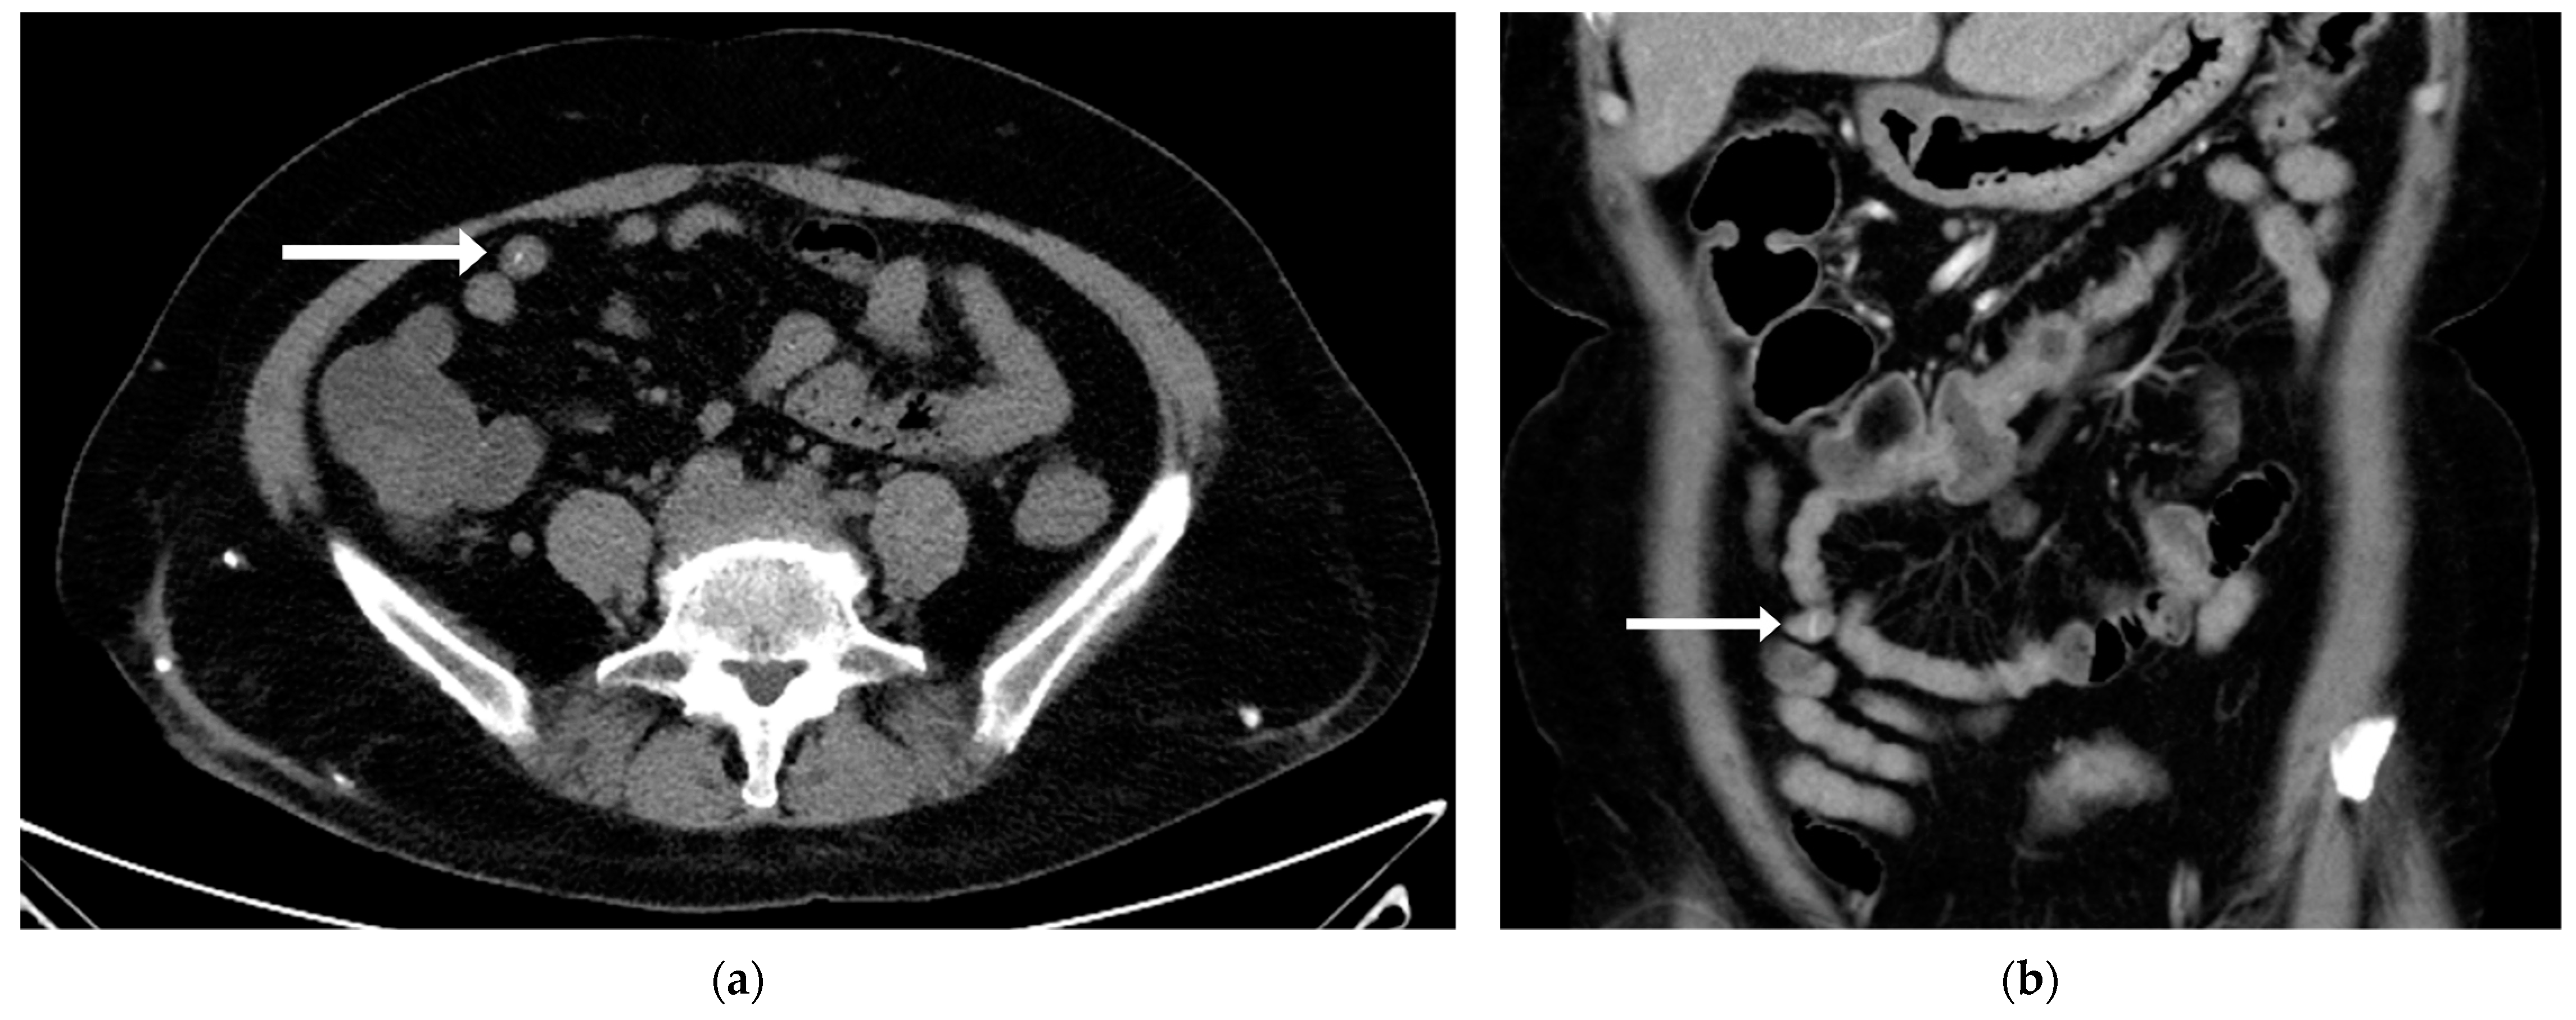

2. Case Presentation